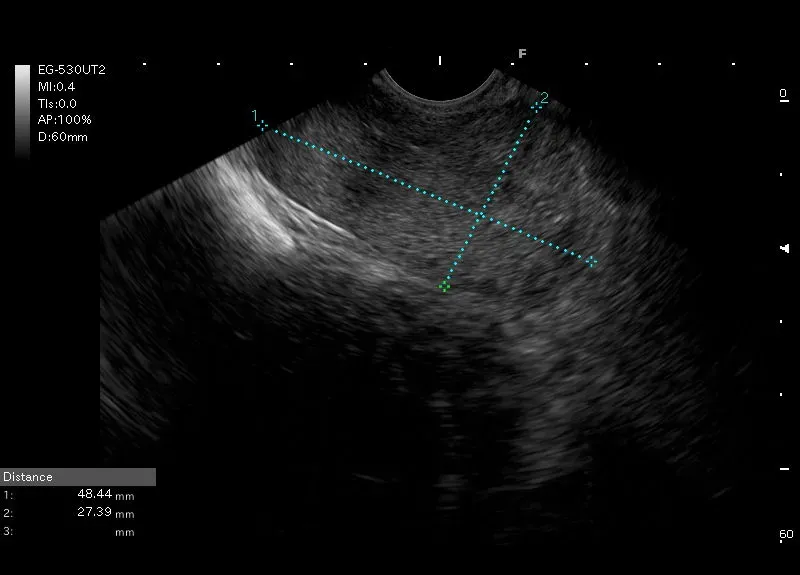

Niejednorodna zmiana przylegająca do lewego płata wątroby i żołądka, bez wyraźnej granicy z miąższem wątroby.